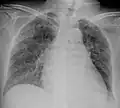

X-ray, 13 days after onset, showing bilateral interstitial infiltrates